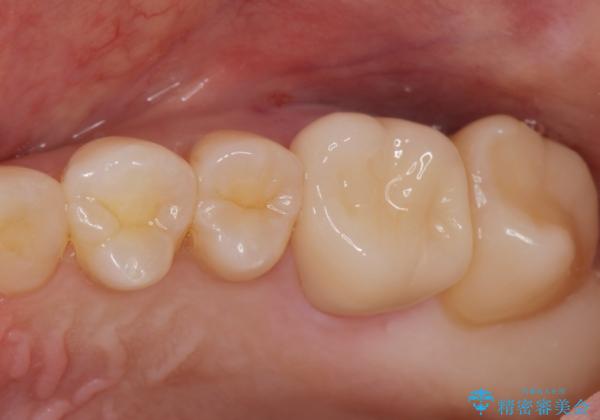

[歯と歯の間の虫歯] ジルコニアクラウン

- メンテナンスの患者様です。レントゲンで歯と歯の間の虫歯が発見されたため治療を行うことになりました。

歯質全体が粗造になっており、インレー治療だと虫歯になる可能性があるので被せ物での治療となりました。

適合が良い被せ物が入りました。

毎日フロスや歯間ブラシを行うことで歯と歯の間が虫歯になるリスクが低くなります。